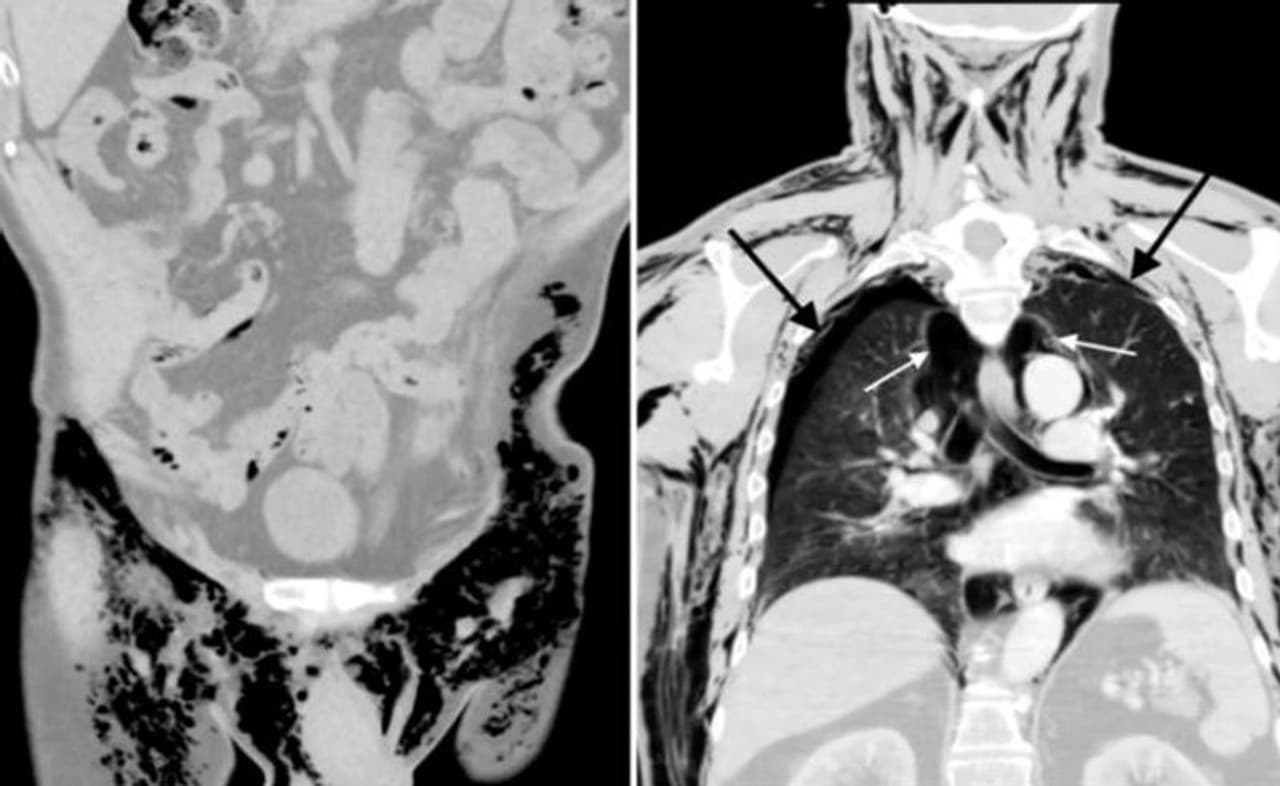

यह शख्स जब डॉक्टर के पास गया तो और अपनी परेशानी बताई तो डॉक्टरों ने पूरे शरीर की हर जरूरी जांच कर ली। रिपोर्ट में सामने आया कि सीटी जैसी जो आवाज निकल रही है, वह उसके अंडकोष यानी स्क्रोटम से आ रही है। ठीक से सांस नहीं ले पाने की वजह से उसके शरीर में निर्धारित मात्रा से अधिक हवा भर गई है। इससे उन्हें व्हिसलिंग स्क्रोटम हो गया है। डॉक्टरों के अनुसार, यह बंदा पहला ऐसा आदमी है, जिसे यह बीमारी हुई है। अमरीकी जर्नल ऑफ केस स्टडी में इस बारे में जानकारी दी गई है।

डॉक्टरों ने बताया कि इस शख्स को तुरंत इलाज की सलाह दी गई। अगर वे ऐसा नहीं कराते तो ह्रदय और फेफड़े हमेशा के लिए क्षतिग्रस्त हो सकते थे। इस स्थिति में उनकी मौत भी हो सकती थी। दरअसल, स्क्रोटम यानी अंडकोष के बायीं तरफ एक घाव था और आवाज इसी जगह से आ रही थी। पांच महीने पहले ही इस शख्स की वहां सर्जरी हुई थी और कुछ गड़बड़ी की वजह से वहां यह घाव हो गया था। हालांकि, एक अस्थायी व्यवस्था कर दी गई है, जिसके तहत शरीर में मौजूद हवा को निकालने के लिए सीने में प्लास्टिक के दो ट्यूब लगाए गए हैं। इससे फेफड़े के संक्रमण को काफी हद तक कम कर दिया गया है।